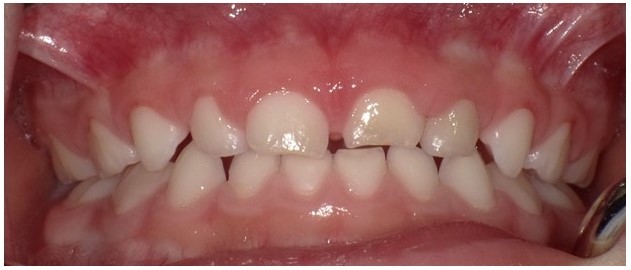

①哺乳う蝕

糖分を多量に含んでいる母乳を寝かしつけながら飲ませることで生じるう蝕のことを「哺乳う蝕」と呼んでいます。1歳半頃までにスムーズに卒乳できればよいのですが、就寝時にぐずったりすると根負けしてしまい、卒乳の時期が遅くなってしまうことがあります。哺乳う蝕では、一般的にう蝕にならない下顎前歯部までも侵されてしまうことが特徴であり、3歳以前に多くの歯にう蝕が発生してしまいます(図4)。そこで、1歳代のお子さんの保護者と接する機会があれば、卒乳に関して話題にしていただくのがよいと思います。また、「哺乳瓶う蝕」という用語もあります。これは、哺乳瓶に糖分を多量に含んでいる飲料を入れて与えることで生じるう蝕です。長時間にわたって砂糖を含む飲料を摂取することになるため、哺乳う蝕と同様に、低年齢にも関わらず多くの歯にう蝕が生じます。

(図4)哺乳う蝕の一例(2歳6か月男児)